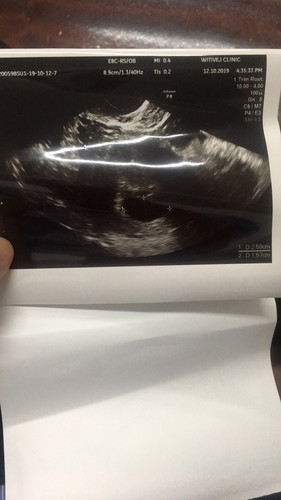

อัลตราซาวน์ครั้งแรกทางช่องคลอดตอน 7 wk 0day เจอเเค่ถุงครรภ์ไม่เจอตัวน้องเครียดมากๆ กลัวเป็นท้องลม มีคุแม่ท่านไหนมีประสพการณ์แบบนี้ รบกวนช่วยแชร์ด้วยนะคะ

เจอเเค่ถุงครรภ์ แอบกังวลเรื่องท้องลม คุณแม่ท่านไหนมีประสพการณ์แบบนี้มั้ยคะ